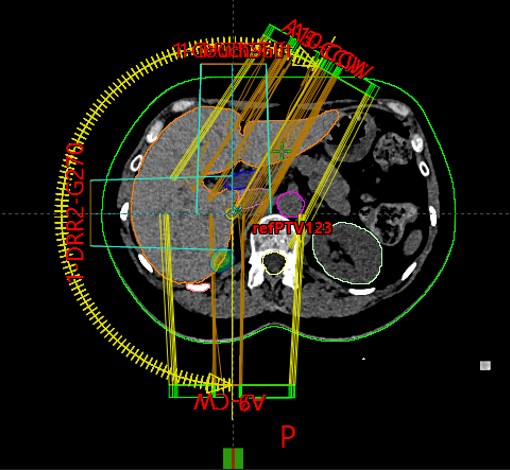

SABR meta hepatis et pelvis (21.11.2017.)